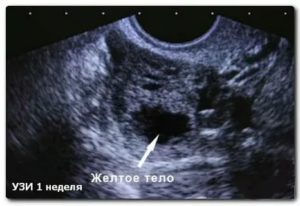

Данный термин определяется как временная железа, которая продуцирует гормоны. По структуре она является неоднородной, имеющая неправильную форму и края на изображениях УЗИ. Формирование происходит на левом либо правом яичнике в период овуляции, 10-16 сутки цикла.

На УЗИ желтое тело определяется как округлое неоднородное образование.

Его видно и при методике исследования через брюшную стенку (трансабдоминальная методика УЗИ), но более достоверные результаты диагностики получают при трансвагинальном методе с использованием внутривагинального датчика.